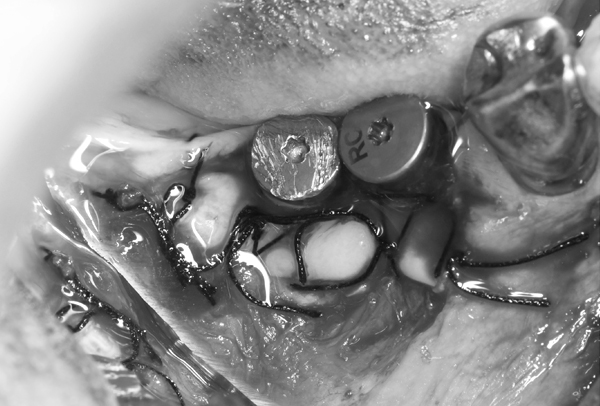

症例6. 再生療法-EPPT-

| EPPT(Entire Papilla Preservation Technique) 歯冠乳頭を保存し、 治癒と審美的な予後を 期待できる術式 |

人工骨の填入 |

![]() |

|

| 縫合 |

| 術後 | ほとんど歯冠乳頭が 下がることなく、 欠損部位に 骨様組織が確認できる |

術前後の比較

| 術前 | 術後 |